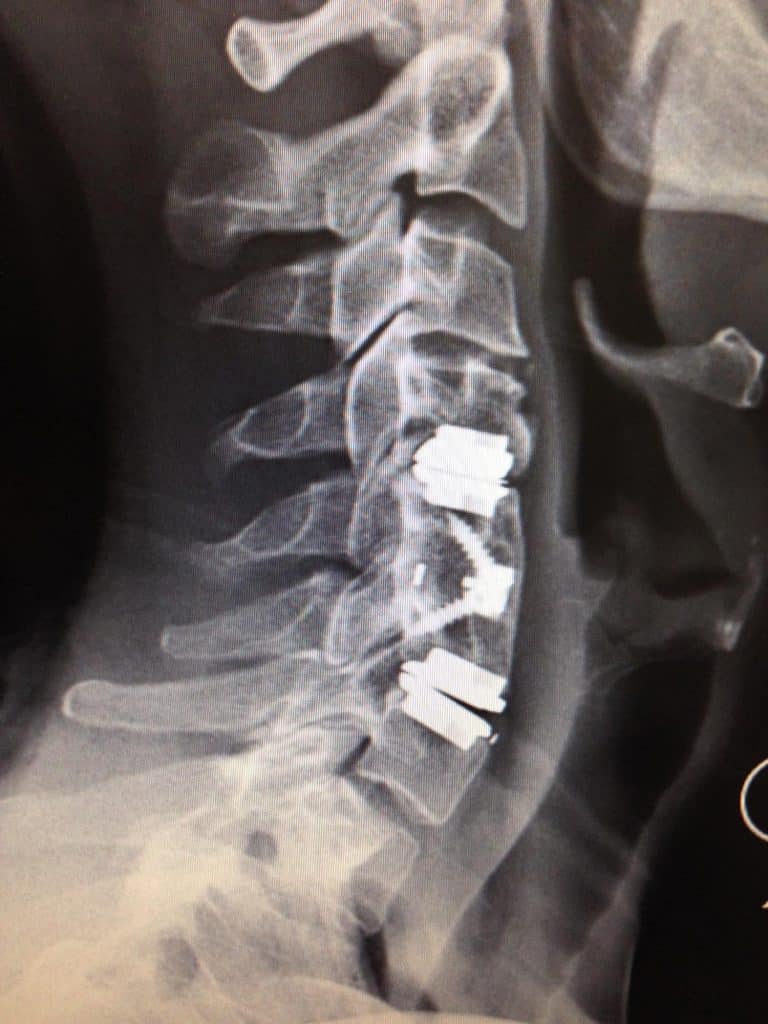

Digital X-rays

No Need To Go Multiple Places with Onsite Digital X-rays

Nexus Chiropractic has a state of the art, top of the line, digital x-ray system in house. We are able to to take the necessary x-rays and analyze the images for your care without having to send you to another facility thus reducing the need for multiple visits, running around, and waiting for another office to send images over.